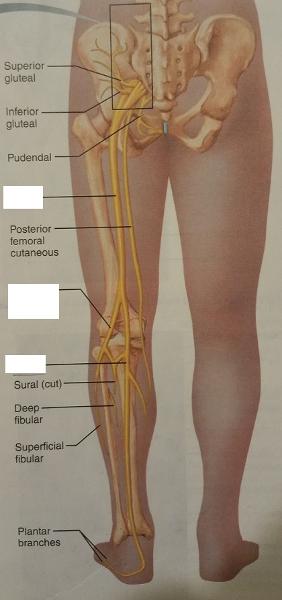

The sacral plexus arises from the ventral rami of which lumbar and sacral nerves?

L4-S4

1. The nerves of the sacral plexus supply which 2 body parts?

2. The nerves of the sacral plexus also supply which 2 groups of fibers of which 2 body parts?

1. The sacral plexus nerves supply...

- buttock

- posterior surface of the thigh

2. The nerves of the sacral plexus also supply...

- sensory fibers of the leg and foot

- motor fibers of the leg and foot

What is the major peripheral nerve of the sacral plexus?

Sciatic nerve

The sciatic nerve arises from the ventral rami of what lumbar and sacral nerves?

L4-L5 and S1-S3

What is the largest nerve in the body?

Sciatic nerve

The sciatic nerve serves which group of muscles of which body part and also, which general feature of that body part?

Serves the flexor muscles of the posterior thigh and the skin of the posterior thigh

In the popliteal region, the sciatic nerve divides into which 2 nerves?

1. common fibular nerve

2. tibial nerve

The common fibular nerve and the tibial nerve supply the muscles of which body part, and what general feature of that body part?

Supply the leg muscles and the skin of the leg

1. Give an example of a muscle served by the common fibular nerve.

2. Give an example of a muscle served by the tibial nerve.

1. Extensor digitorum longus

2. Flexor digitorum longus

The common fibular nerve arises from the ventral rami of what lumbar and sacral nerves?

L4-S2

The tibial nerve arises from the ventral rami of what lumbar and sacral nerves?

L4-S3

Identify the blanks.

Identify the blanks.

Identify the blanks.

Identify the blanks.

Identify the blanks.

Identify the blanks.

Identify the blanks.

Identify the blanks.

Identify the blanks.

Identify the blanks.